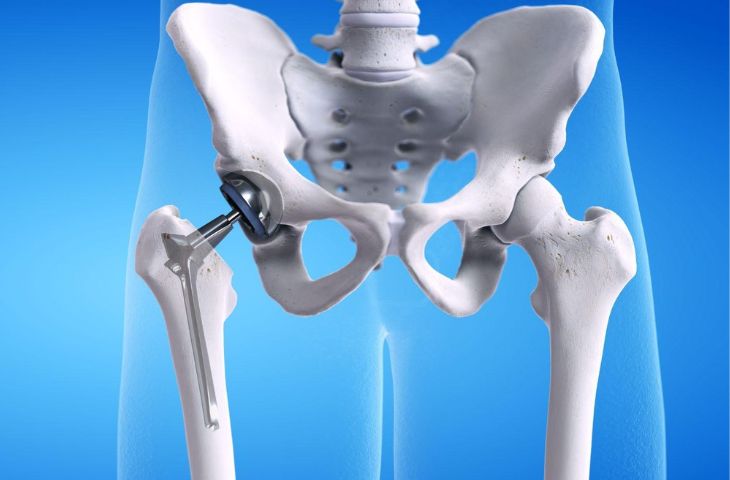

- Thay khớp háng toàn phần: được chỉ định cho bệnh nhân bị hoại tử chỏm xương đùi, gãy cổ xương đùi không có khả năng bảo tồn, thoái hóa khớp háng nặng không đi được, bệnh lý vùng cổ xương đùi như bướu… Thay khớp háng toàn phần được thực hiện bằng cách ghép khớp nhân tạo có chức năng tương tự khớp tự nhiên vào cơ thể.

Phẫu thuật thay khớp háng